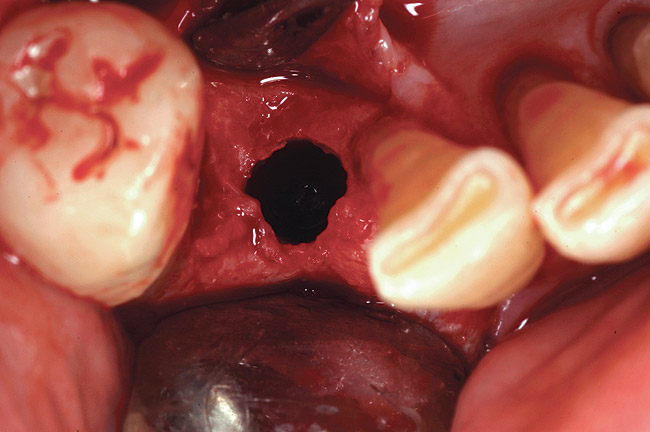

The grafted sites were followed clinically and radiographically throughout the healing period. Healing of the residual crestal defects (if present) also was followed. At approximately 6 months, the patients returned for graft analysis and placement of implants. Clinical photographs and radiographs were taken preoperatively. After administration of local anesthesia and minimal flap elevation, measurements of alveolar ridge width were repeated to compare with the preoperative alveolar dimensions (Figure 4). The coronal portions of the regenerated sites were evaluated for the presence of residual graft material. Preparation of the osteotomies was initiated with a bone trephine to sample the coronal 5 mm to 7 mm of socket healing (Figure 5). The placement of appropriately sized dental implants was performed according to the manufacturer’s recommendations, and the flaps were sutured to facilitate both soft- and hard-tissue healing.

Figure 4  Occlusal view of the healed bony ridge, taken at the time of implant placement.

Figure 4

Figure 5  Occlusal view of the osteotomy site after retrieval of a core of regenerated material.

Figure 5